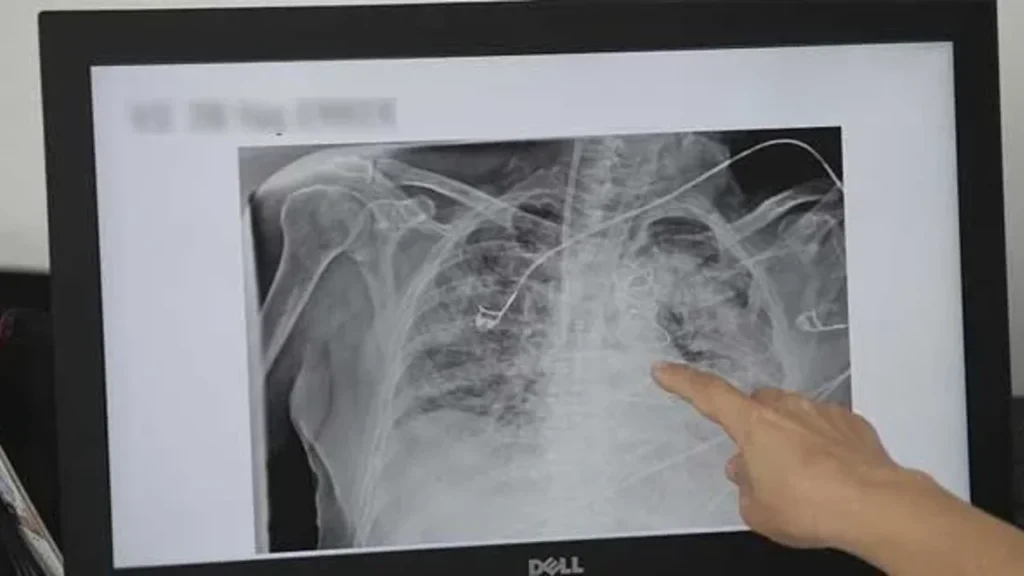

Hangi Testler Ve Muayene Yaklaşımı Öne Çıkar?

Uzman değerlendirmesinde şikâyet süresi, maruziyet öyküsü ve muayene bulguları önemlidir. Gerekli görüldüğünde akciğer filmi, solunum fonksiyon testi veya ileri görüntüleme gibi yöntemler kullanılabilir.